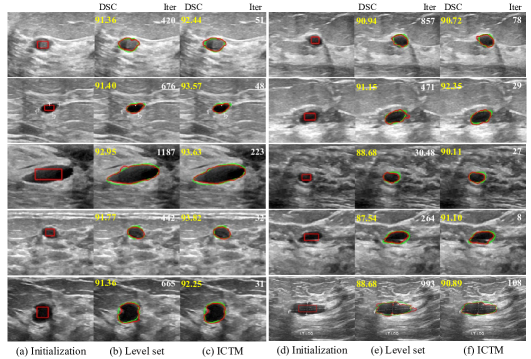

4.2 Breast nodule segmentation in ultrasound images

To validate the performance and efficiency of our method on real images, we apply it to breast nodule segmentation in ultrasound images. In this experiment, we use the BUSI dataset [1] and select 100 random benign breast ultrasound images to compare the efficiency between the LSM and the ICTM. The same rectangle initialization is generated based on ground truth for images. The width and height of each rectangle is half of the major axis and minor axis of the ground truth’s bounding box, respectively. For a fair comparison, we apply grid search to each method to find the best set of hyper-parameters that can achieve the best average Dice similarity coefficient (DSC) on this dataset. The main contribution in this work is a more efficient method. Thus we try our best to achieve the best performance for both LSM and ICTM, and then compare their running efficiency. Specifically, we set α=5𝛼5\alpha=5, λ=3𝜆3\lambda=-3, μ=0.2𝜇0.2\mu=0.2 and Δt=1Δ𝑡1\Delta t=1 for the LSM, respectively. For ICTM, we set τ=2𝜏2\tau=2 and λ=0.2𝜆0.2\lambda=-0.2, respectively.

Figure 2: Breast nodule ultrasound image segmentation results. Columns (a) and (d) are input images and corresponding initialization (red rectangles). Columns (b) and (e) are segmentation results of the LSM. Columns (c) and (f) are segmentation results of Algorithm 1. Green and red contours denote ground truths and segmentation results, respectively. Yellow and white numbers at the top of images indicate segmentation accuracy (Dice similarity coefficient (DSC)) and the number of iterations. See Section 4.2.

Table 2 shows the quantitative results of breast ultrasound image segmentation. The proposed ICTM method is slightly better than the LSM with 1.35% improvements in average DSC. The number of average iteration of our ICTM is 58, which is 12.4 ×\times fewer than the LSM. For the average running time, the LSM takes about 74 seconds per image while the proposed ICTM only needs 0.66 seconds per image, achieving more than 100 times acceleration. Figure 2 displays 10 random selected images with segmentation results by the LSM and our ICTM, with corresponding DSC (yellow) and running time (white) printed on. The two methods start with the same initialization, and we observe that

• The ICTM achieves similar or even better segmentation results than the LSM, indicating the feasibility of applying the ICTM into real image segmentation.

• The ICTM requires much less running time than the LSM, implying the high efficiency.